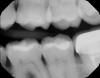

Fig 10. Decay evident, teeth J and K, on x-ray of caries-prone 6-year-old patient.

Figure 10

Fig 11. Transillumination image confirmed caries.

Figure 11

In another case of a caries-prone 6-year-old patient, the clinician, who generally avoids taking x-rays on children, opted to take them this time because lesions can grow rapidly.13 The transillumination caries detector also was used to attain a more complete diagnosis and to find problems as early as possible. Decay appeared on both the x-ray (Figure 10) and the CariVu image (Figure 11). Viewing the situation from multiple perspectives enables treatment to be as conservative as possible because the clinician can pinpoint exactly where the decay is present on the tooth.